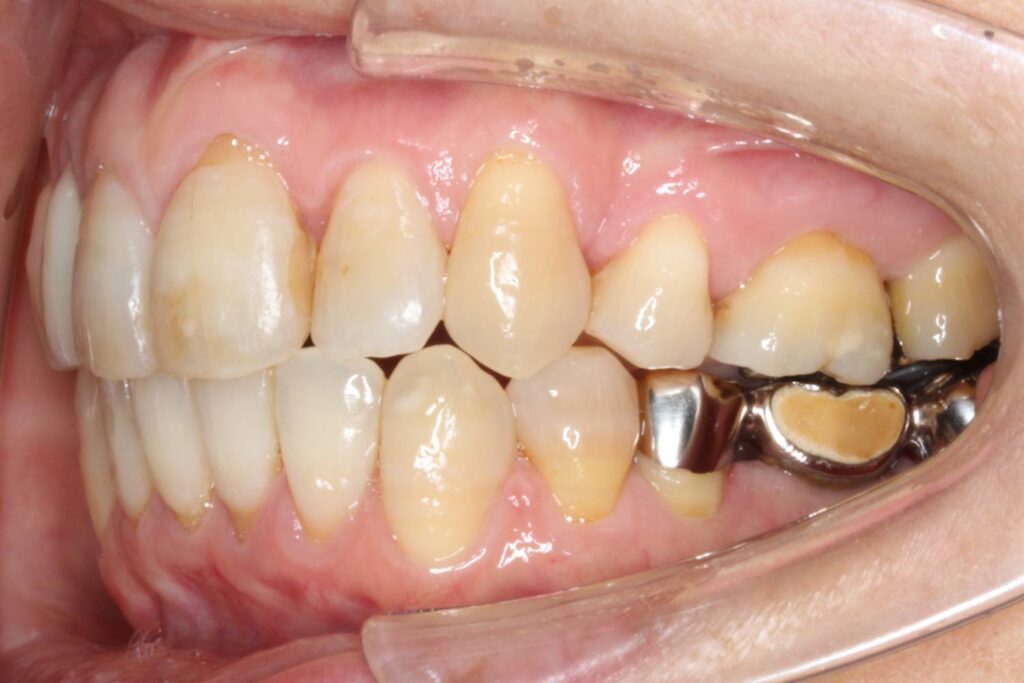

治療後は、上下顎の中心が一致し、でこぼこが解消されて前歯の印象が良くなりました。

また、ブリッジの部分も無事に壊さずに、上顎の歯と問題なく噛み合っています。

After